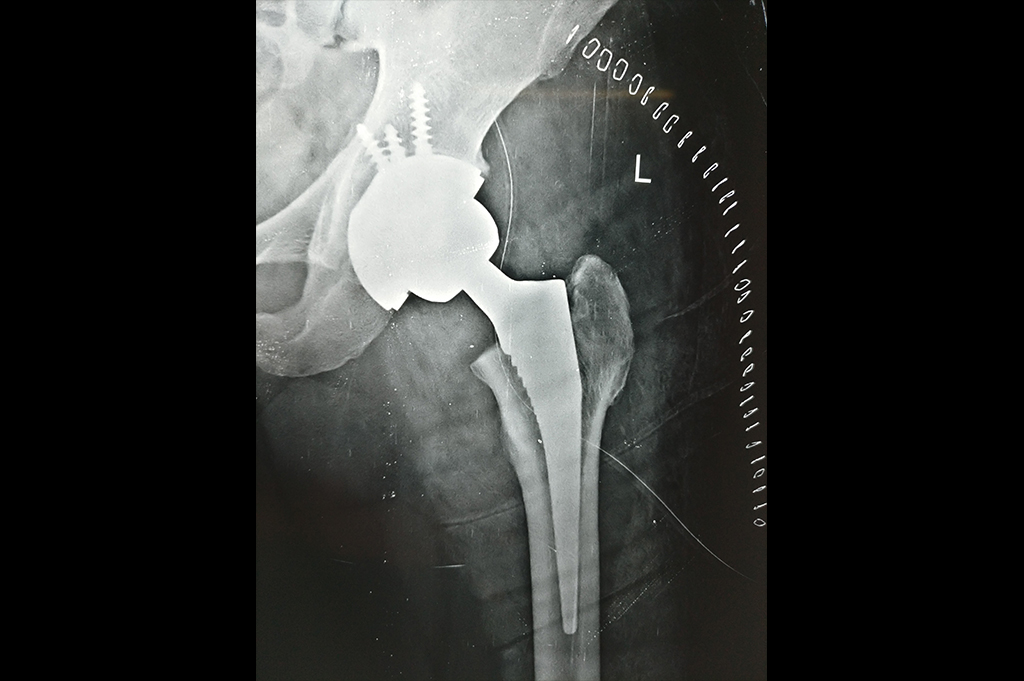

Total Hip Replacement - THR